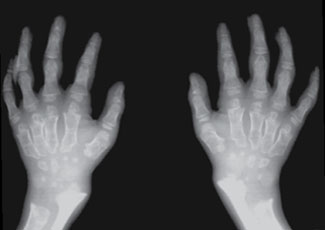

Other X-ray findings in the hands:

- Bullet-shaped phalanges1

子彈形指骨 - Short, proximally pointing metacarpals2

Pediatric patient with MPS. Note the classic, very severe proximal pointing, thin cortices, small/irregular carpal bones, and ulnar hypoplasia.3

Pediatric patient with MPS. Note the severe proximal pointing, wide metacarpals and phalanges, and thin cortices.2